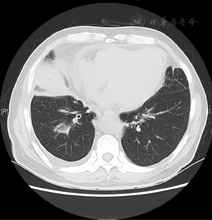

患者男性,58岁,主因"双侧季肋部疼痛伴活动后气短1个月"于2015年12月8日入院。1个月前患者无明显诱因出现双侧季肋部疼痛,深吸气加重,上2层楼后出现呼吸困难,无发热、咳嗽。外院行胸部CT提示"双肺炎性实变,左下叶局限性肺不张,右侧少量胸腔积液,心包少量积液"(图1),予静脉应用莫西沙星8 d,患者自觉症状无改善,并出现双肩和双下肢酸痛,双足背皮肤麻木。7 d前于我院就诊,心电图V4~V6导联ST段压低,Ⅰ、Ⅱ、V4~V6导联T波倒置(图2)。肌酸激酶同工酶MB (CK-MB) 31 U/L,肌钙蛋白T 1.4 μg/L,N末端B型利钠肽原(NT-proBNP) 4 399 ng/L。以"心力衰竭、急性非ST段抬高型心肌梗死(NSTEMI)"收入我科。自发病以来,患者神清,家属觉患者言语减少,反应迟钝,夜间睡眠较差,大小便无明显改变,体重近1个月下降5 kg。既往史:过敏性鼻炎病史13年,3年前开始规律应用丙酸氟替卡松喷雾剂,控制稳定。支气管哮喘13年,3年前开始应用沙美特罗替卡松,控制稳定。高血压病史15年,2型糖尿病史10余年,吸烟30年,25支/d,已戒11年,无饮酒嗜好。否认家族性遗传病史。入院查体:体温36.8 ℃,脉搏90次/min,呼吸16次/min,血压102/70 mmHg(1 mmHg=0.133 kPa)。神清,对答反应迟钝,计算力、近记忆力差。右肩胛下角线第9肋间以下叩诊浊音,听诊呼吸音减低,双下肺闻及吸气相湿啰音,无胸膜摩擦音。心界向左扩大,心率90次/min,律齐,心音有力,A2>P2,未闻及杂音,无心包摩擦音。腹部查体未见异常,双下肢胫前可凹性水肿。四肢肌力Ⅴ级,左小腿针刺感稍差。血常规示白细胞计数11.8×109 /L,血红蛋白130 g/L,血小板计数251×109 /L,嗜酸性粒细胞42.4%明显升高。尿常规示尿蛋白(1+),未见镜下血尿。

进一步完善检查,血沉81 mm/h,C反应蛋白92.3 mg/L (正常值<8.0 mg/L)。免疫球蛋白七项:IGA 5.5 g/L(正常值0.7~3.8 g/L),IGE 770.6 g/L (正常值<100 g/L),IGG、IGM、总补体、补体C3和补体C4正常。髓过氧化物酶抗中性粒细胞胞质抗体(MPO-ANCA)、丝氨酸蛋白酶3抗中性粒细胞胞质抗体(PR3-ANCA)、抗核抗体、抗ENA抗体谱、抗dsDNA抗体和抗脑组织抗体均为阴性。便常规、肝功能、肾功能、甲状腺功能、凝血功能均未见异常。超声心动图示心内膜略增厚,左心室内血栓前状态[1],左心房增大,室间隔增厚(12.2 mm),左心室舒张功能减退,左心室射血分数(LVEF) 55%,心包积液(少量)伴纤维素渗出(图3)。支气管肺泡灌洗液的细胞中嗜酸粒细胞占97%,提示存在肺部嗜酸性粒细胞浸润。复查胸部CT较1个月前无明显变化。颅脑磁共振成像示双侧半卵圆中心、右侧侧脑室后角见斑点状高信号影。肌电图示右腓总神经复合肌肉动作电位(compound muscle action point,CMAP)未测出,左腓总神经、双胫神经远段CMAP波幅下降,左三角肌、双股四头肌示肌源性损害,提示患者存在神经及肌肉损害。肌肉、神经、皮肤活检病理示左腓肠肌中度肌源性损害,左腓总神经损害以髓鞘改变为主,筋膜及皮肤可见间质小血管壁炎症细胞浸润,以淋巴细胞为主,偶见嗜酸性粒细胞。骨髓穿刺示嗜酸粒细胞增多,较成熟。基因分型未见FIP1L1-PDGFRα融合基因。荧光染色体原位杂交未发现FIP1L1/PDGFRα融合基因、未发现PDGFRB基因重排。